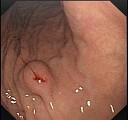

问题 女,28岁,间歇性上腹痛腹胀4年,无呕吐。抗酸制剂治疗无效,查体上腹轻压痛,B超肝查未见异常,胃镜检查如图。最有可能性的诊断是 ( )

选项 A.消化性溃疡 B.胃癌 C.胆囊炎 D.胃下垂 E.萎缩性胃炎

答案 D